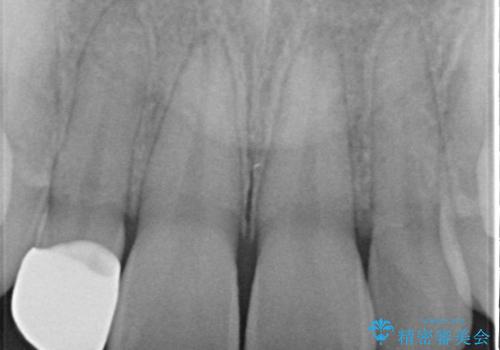

- 上の歯の隙間が気になるとのことで来院されました。

上顎の正中に隙間があり、右上の2番目の歯が通常の歯より小さい矮小歯でした。

正中の隙間をインビザライン矯正で閉鎖して、右上の2番目の歯にはセラミックを装着する計画としました。